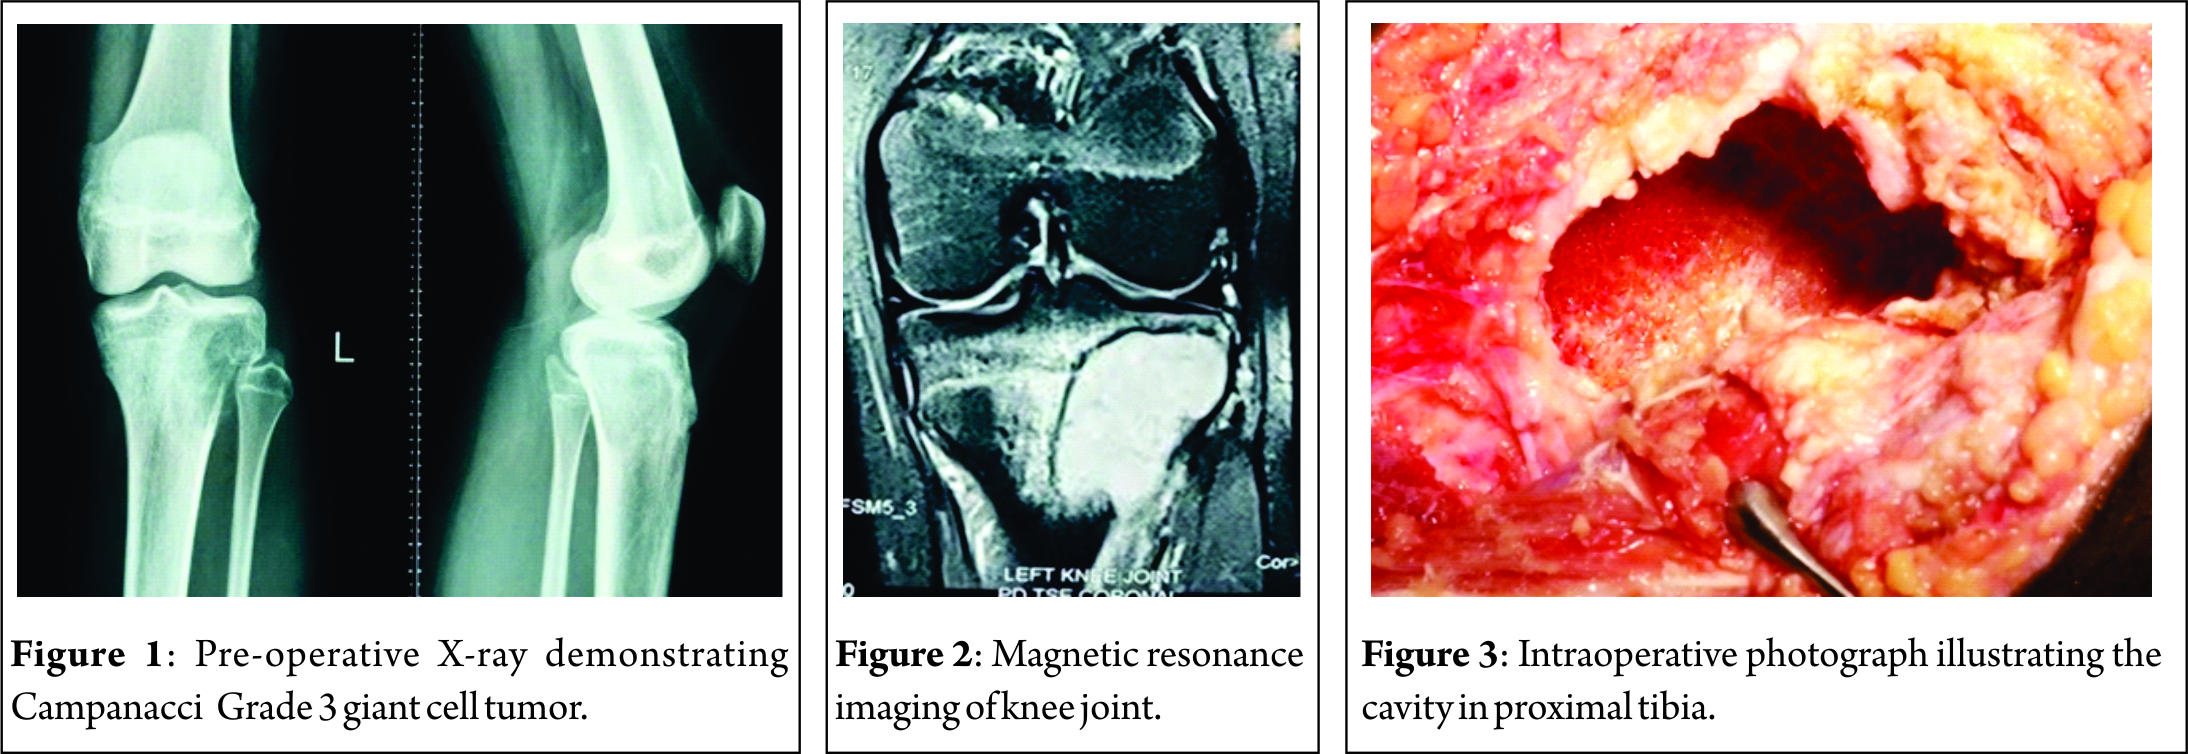

A 15-year-old girl presented to us with a dull pain in the left knee for 3 months and difficulty in squatting. On clinical examination of her left knee joint, there was no mass palpable. The terminal range of movement at the knee joint was restricted. There were no signs of inflammation. Laboratory investigations revealed C-reactive protein to be raised to 7.1 mg/dl, a normal alkaline phosphatase of 363U/L, and a raise derythrocyte sedimentation rate of 40. Radiographs of the knee joint showed an eccentric epiphyseal metaphysealosteolytic lesion of the left proximal tibia with anterolateralcortical breach. This lesion was graded as a Campanacci Grade 3 tumor (Fig. 1). Magnetic resonance imaging (MRI)showsa well-defined fairly homogenous hypointense lesion involving the proximal tibia with infiltration into surrounding soft tissue. Heterogeneously enhancing lesion with central non-enhancing hypointense areas was observed on T1W. A few central hyperintensities may represent cystic/hemorrhagic areas(Fig. 2).

An anterolateral approach to the proximal tibia was chosen for this patient keeping the possibility of knee joint involvement in mind. The iliotibial band was incised, and the proximal tibia explored to delineate the boundaries of the lesion. The lateral cortex of the proximal tibia was nibbled out to enter the cavity (Fig. 3). A thorough curettage was done using a bone gouge. The cavity was washed with hydrogen peroxide repeatedly to induce thermal necrosis of the remnant tumor cells. A final curettage of the inner margins was done using a burr. Subchondral bone was observed to be normal, and hence, joint was preserved. The cavity was washed again with hydrogen peroxide, and antibiotic-coated bone cement was used to fill up the entire dead space in the cavity. Once the cement was set, a local wound wash was given at the incision site and wound closed in layers. The curetted material was sent for histopathological studies(Fig. 4).

Post-operative radiographs confirmed that the cavity had been completely packed with cement and no dead space was evident (Fig. 5). The post-operative period was uneventful. Weight-bearing was initiated 10 days after surgery. She achieved full range of motion of her knee joint in 3 weeks.

Multiple sections showed many multinucleated osteoclast-like giant cells, uniformly distributed in sheets of spindle to polygonal cells. There was no cellular atypia. Spindle-shaped tumor cells were seen having elongated ovoid nuclei with bland nuclear chromatin and scant to moderate amount of amphophilic cytoplasm. Features were strongly suggestive of GCT (Fig. 6).